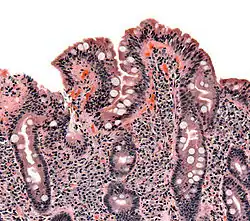

Biopsies of the small bowel in SIBO can mimic celiac disease, with partial villous atrophy.